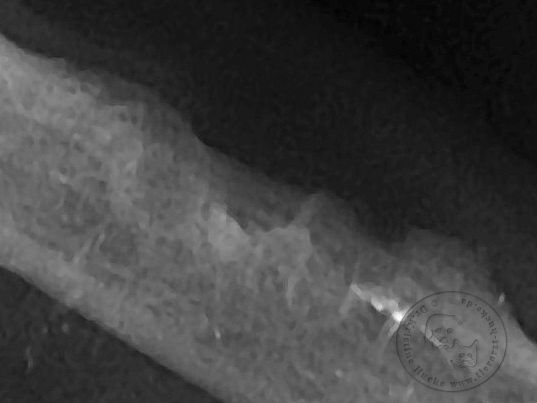

Wie es schon zu vermuten war lässt sich der Zahn nicht komplett extrahieren, selbst eine Teilung in der Mitte mit einem speziellen Zahnbohrer reicht nicht um die tiefsitzende Wurzel unterhalb des porösen Zahnhalses in einem Stück zu entfernen.

Hier nochmal eingezeichnet

Ist die vordere Wurzel des Prämolar 4 und die beiden Wurzeln des Molar 4 vorsichtig herausgearbeitet sowie das noch zurückgebliebene letzte Zahnfragment entfernt, fehlt noch die Kontrolle ob wirklich alles entfernt ist.

Dies geht nur mit einer digitalen Dentalröntgenaufnahme!